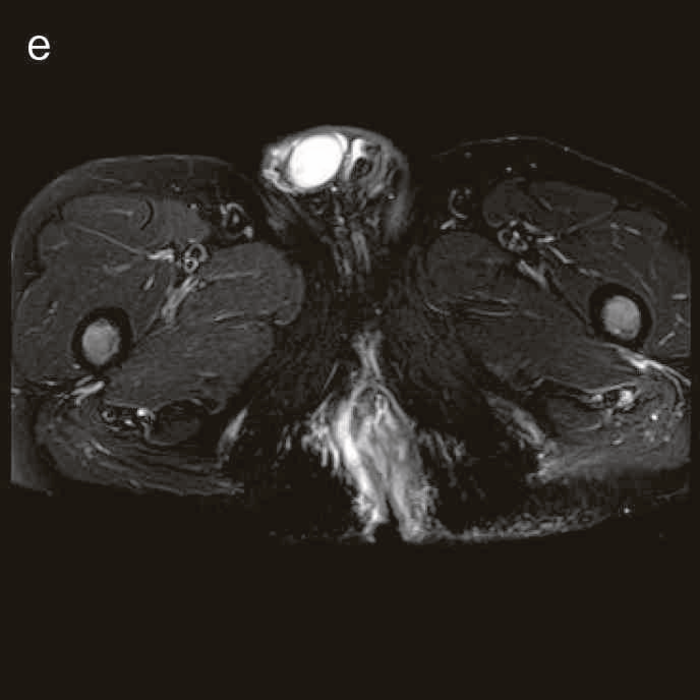

2. その他画像診断

内視鏡以外の画像診断には,超音波検査,CT検査,MRI検査などがあるが,CD関連腫瘍に関する診断は,やはり未確立である4)。こうしたcross sectional imagingにおいては,CDの炎症による腫瘤や膿瘍との鑑別が課題となる5)。CD関連消化管癌では病変が房状を呈することがあるが(図27),早期の病変を診断することは困難である。臨床では,痔瘻や肛門周囲膿瘍の評価のためのcross sectional imagingによる検査でCD関連消化管癌の可能性がある所見を拾い上げられるかがポイントとなるが,確定診断後に画像診断所見を見直した際に,所見に気付くことも少なくない。また確定診断のためには,内視鏡検査による生検や外科的な生検か細胞診を行う必要がある。

図27 CD直腸肛門部癌の骨盤造影MRI検査像

直腸内に増強効果を受ける分葉状の腫瘤を認める。